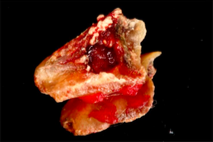

A 65-year-old female on antihypertensives and immunosuppressants presented with severe gum swelling, inability to chew, and difficulty maintaining oral hygiene. This led to multiple decayed and periodontally compromised teeth, worsening her overall condition.

Drug-influenced gingival overgrowth or ‘DIGO’ in short, manifests as abnormal swelling of the gingiva.

- The condition is usually caused by adverse reactions to certain drugs such as antihypertensives, anticonvulsants or immunosuppressants.

- As the gum tissues become significantly larger, it may impede normal masticatory function, daily oral hygiene, and aesthetics, severely diminishing one’s quality of life. (Sabarudin et al. 2022)

- Surgical removal of excessive gum tissues and extraction of multiple poor prognosis teeth were carried out as well